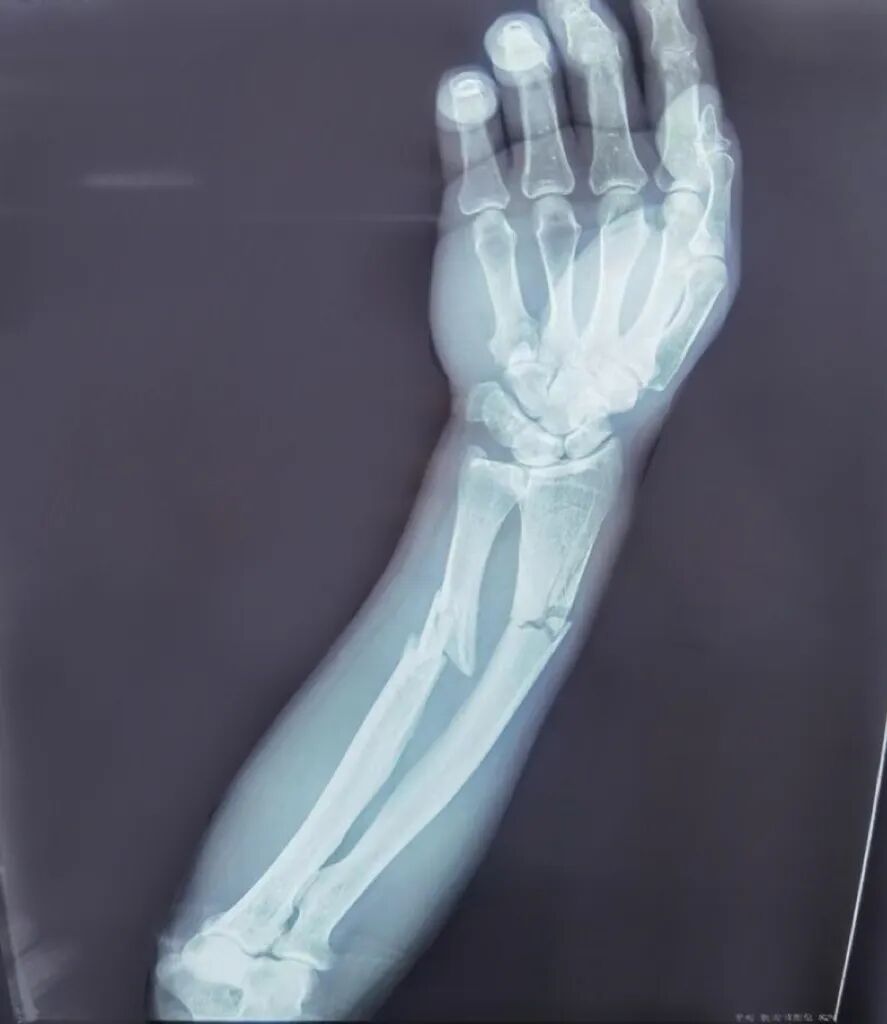

桡骨远端的骨折需要手术么?

桡骨远端骨折的治疗方式是多种的。比较常见的是常规的切开复位桡骨远端接骨板内固定术,以及微创的闭式复位克氏针固定术。相较于常规方式,微创的治疗方式更容易被患者接受,它有着创伤小、治疗结束后几乎没有明显疤痕、可以进行早期康复锻炼、取出固定物时二次损伤轻微等优势。